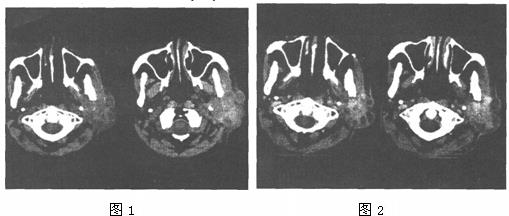

- 单项选择题 女,55岁,鼻咽癌放疗后15年,近1周左耳根部肿涨,无发热,PE://左耳根部皮下们及三个结节,有波动感和轻压痛,CT如图所示,最可能的诊断是()。

- E